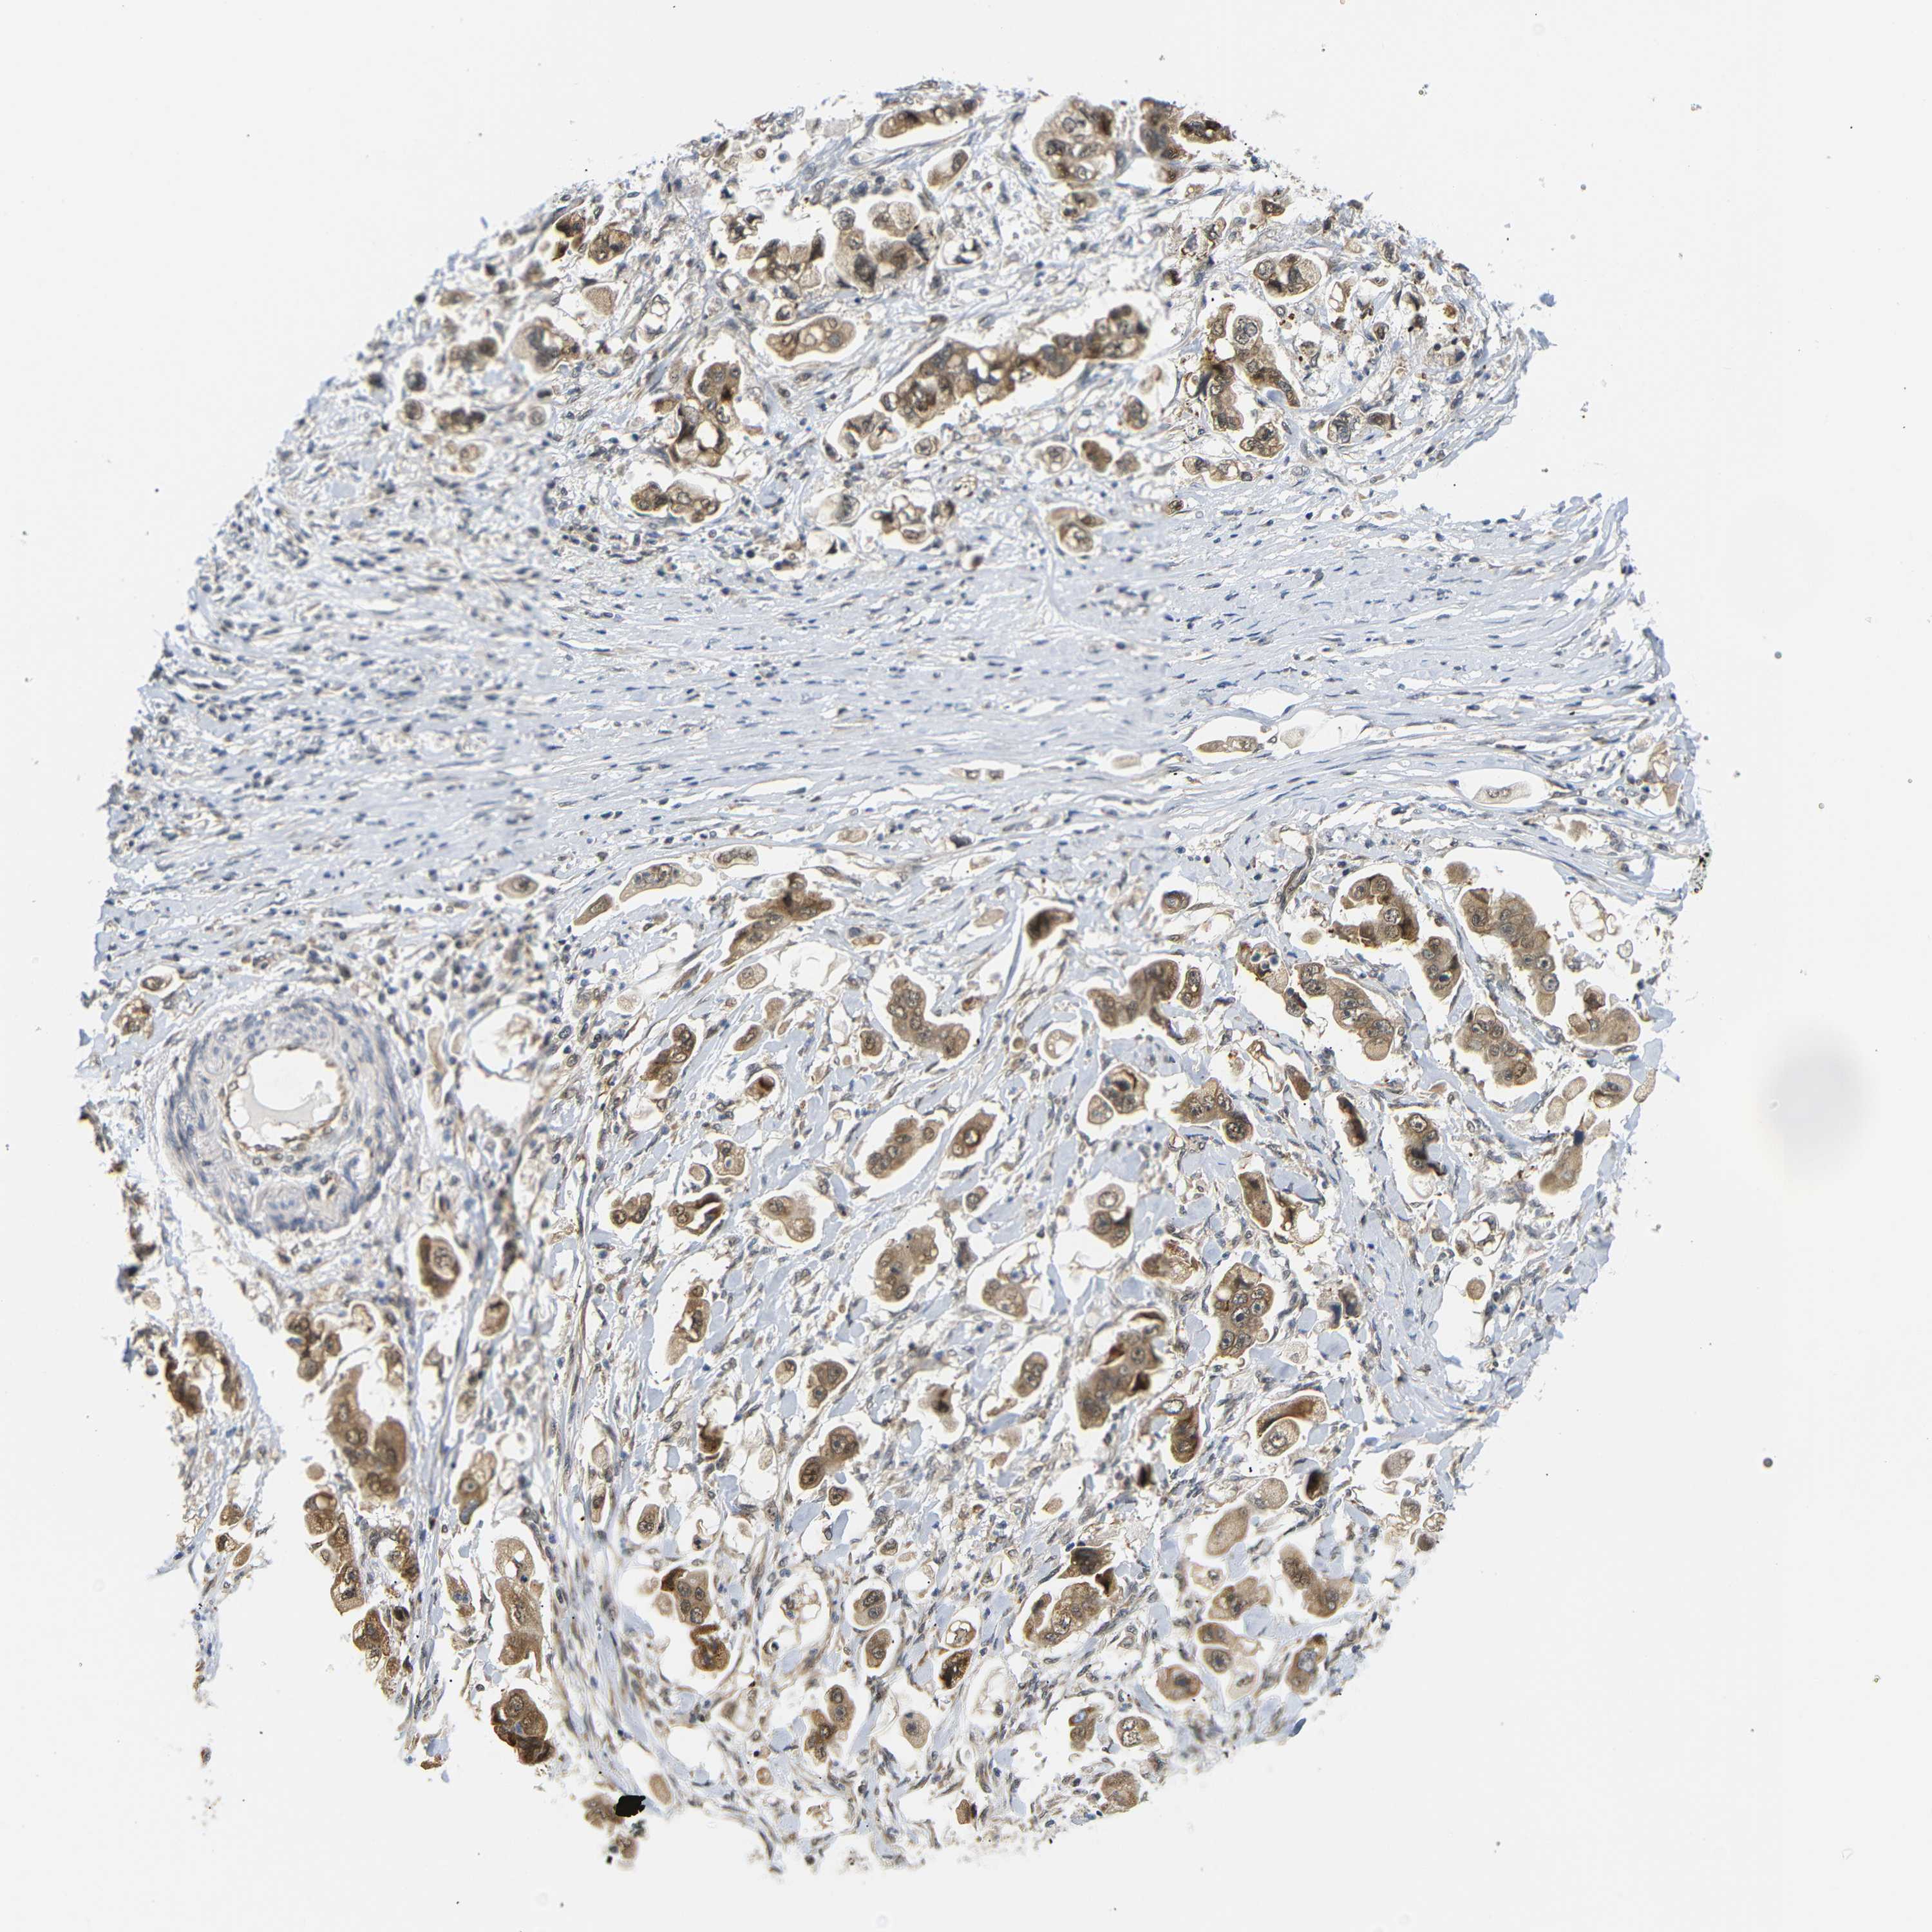

STOMACH CANCER - Protein expressioni

A mouse-over function shows sample information and annotation data. Click on an image to view it in a full screen mode. Samples can be filtered based on level of antibody staining by selecting one or several of the following categories: high, medium, low and not detected. The assay and annotation is described here.

Antibody stainingi

Antibody staining in the annotated cell types in the current human tissue is reported as not detected, low, medium, or high, based on conventional immunohistochemistry profiling in selected tissues. This score is based on the combination of the staining intensity and fraction of stained cells.

Each image is clickable and will lead to virtual microscopy that enables deeper exploration of all samples and also displays staining intensity scores, fraction scores and subcellular localization as well as patient and tissue information for each sample.

Antibody HPA071370

Antibody CAB013080

Staining

High

Medium

Low

Not detected

Intensity

Strong

Moderate

Weak

Negative

Quantity

>75%

75%-25%

<25%

None

Location

Nuclear

Cytoplasmic/membranous

Cytoplasmic/membranous,nuclear

Adenocarcinoma, NOS

Adenocarcinoma, High grade